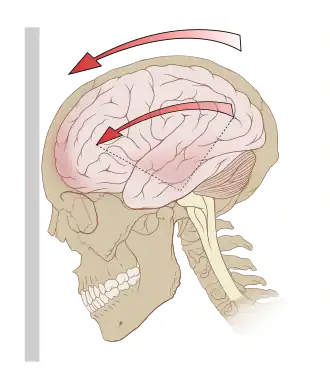

Риск сильного сотрясения мозга заметно возрастает в тех случаях, когда удар по голове или по шлему (каске) не центральный (вызывающий лишь линейные ускорение), а такой, который вызывает одновременно и поворот. При ударах, вызывающих чисто линейное ускорение, травмирование часто происходит лишь тогда, когда удар настолько сильный, что происходит разрушение костей. Мозг, как вода, практически несжимаем, и при линейных ускорениях взаимного перемещения его частей друг относительно друга не происходит. В результате такое воздействие часто не приводит к серьёзным травмам.

Eсли возникает и угловое ускорение, то ситуация резко изменяется. Вращательное движение головы стремиться увлечь за собой периферийные части головного мозга, а они, и центральная часть мозга, по инерции стремится остаться неподвижными. Части мозга стремятся сместиться и относительно неровной внутренней поверхности черепа, и друг относительно друга, что значительно увеличивает опасность. Стремление сместиться создаёт касательные напряжения, которые создают риск разрывов тканей, нервов и сосудов, и соответственно опасность диффузного аксонального повреждения центральной нервной системы[2]. Обычная подвеска касок не уменьшает передачу вращательного движения на голову, что увеличивает риск[3]. Разработаны новые СИЗ головы: если удар стремиться вращать каску, подвеска позволяет ей повернутся относительно головы (в некоторой степени), что ослабляет передаваемые голове «вращающие» силы (подобно тому, как линейное смещение оболочки каски относительно подвески ослабляет прямой удар).